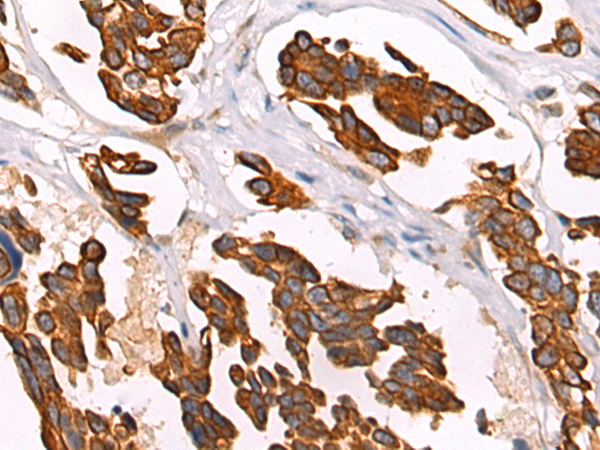

IHC positive control:

Human colorectal cancer and Human thyroid cancer

IHC Recommend dilution:

50-200